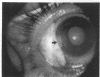

A patient with recurrent squamous cell carcinoma of the conjunctiva was referred with 20/20 vision in an eye with obvious intraocular extension. A modified iridocyclochoroidectomy was performed and the tumour was removed. Three and a half years later the patient's vision is 20/30 and there is no recurrence. This is the first case in which an eye has been successfully salvaged with documented intraocular squamous cell carcinoma of the conjunctiva.